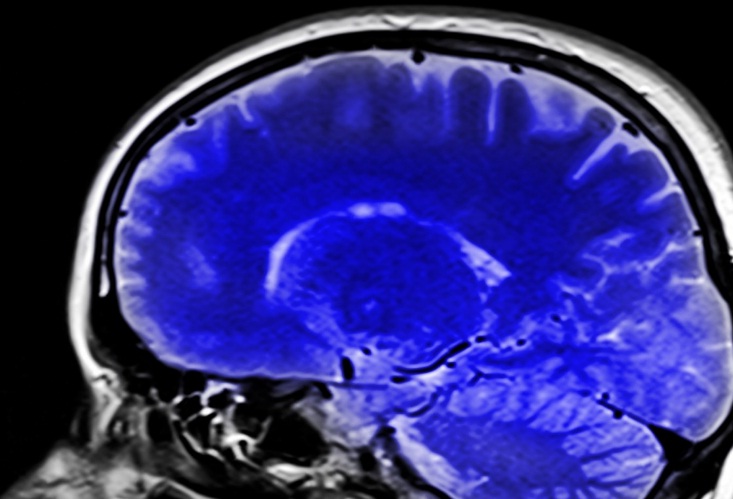

Почти каждый человек после сорока лет сталкивался с «провалами в памяти»: заходишь в комнату и забыл зачем; или никак не можешь вспомнить важную деталь в недавнем разговоре. Автор канала «Павел Корпачев» уверяет, что это могут быть первые «звоночки» болезни Альцгеймера и уверяет, что ее можно предупредить некоторыми продуктами.

Но, во-первых, нужно разобраться с нашей памятью. Углеводы являются одним из ее врагов. Они вымывают из организма важные витамины и магний, а без них мозг постепенно угасает. Поэтому отказываемся от чрезмерного употребления тортиков, сладких булочек и йогуртов.

Для поддержки мозга после сорока нужно обязательно употреблять в пищу некоторые продукты.